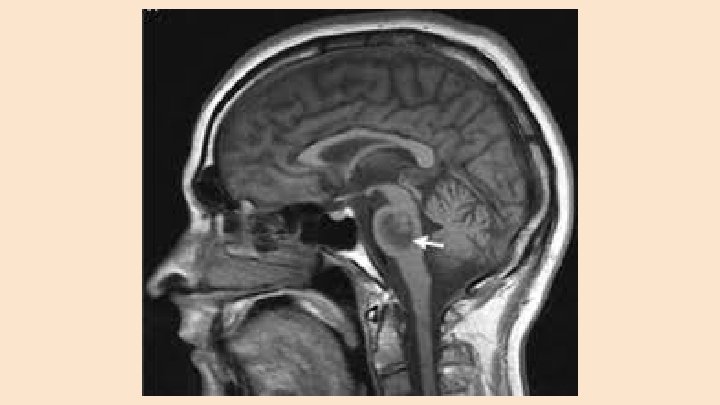

Regulation of Extracellular Osmolality ● It is essential that the Sosm stay within a very specific range to avoid water shifts between the two compartments: extracellular and intracellular ● A decrease in Sosm--most commonly due to a decrease in serum Na--will cause water to flow intracellulary--most critical in brain cells ● Cerebral edema against a non-compliant cranium can result in the development of seizures, significant neurological dysfunction, brain herniation, and ultimately, death

Brain Adaptations to Hyponatremia ● Brain adapts to Sosm, the initial cerebral edema increases interstitial hydraulic pressure, forcing fluid movement out of the brain into the cerebrospinal fluid ● Next, brain cells lose solutes including potassium and organic solutes (osmolytes) thus lowering the intracellular osmolality allowing the brain cells to lose water, coming back to their original volume ● These adaptations occur within the first 24 hours and up to 2 -3 days ● Once hyponatremia is being treated, the reuptake of brain solutes occurs but at a much slower rate and hence treatment much be gradual or serious complications of osmotic demylination syndrome (ODS) may occur--when treating chronic hyponatremia

Osmotic Demyelination Syndrome (ODS) ● Major complication of treatment for hyponatremia ● In chronic hyponatremia, the brain has adapted to the low Sosm by decreasing intracellular water and dumping organic solutes, thus lowering the intracellular osmolality to prevent water shifts. ● In this chronic setting, correction of extracellular osmolality (Sosm)-if too rapid-- will cause water to flow out of the brain cells since they cannot readjust their osmolality as quickly (takes several days) ● This rapid fall in brain cell volume leads to demyelination, for reasons that are not clear.

Osmotic Demyelination Syndrome (ODS) ● Symptoms of ODS include dysarthria, dysphasia, paraparesis, quadriparesis, seizures, lethargy, confusion, disorientation, obtundation, and coma ● Symptoms may be delayed for 2 -6 days after treatment for hyponatremia ● Risk factors for development of ODS include ○ Initial Na of less than 120 meq/L ○ Longer duration of hyponatremia ○ Rapid correction exceeding 8 meq/L in the first 24 hours